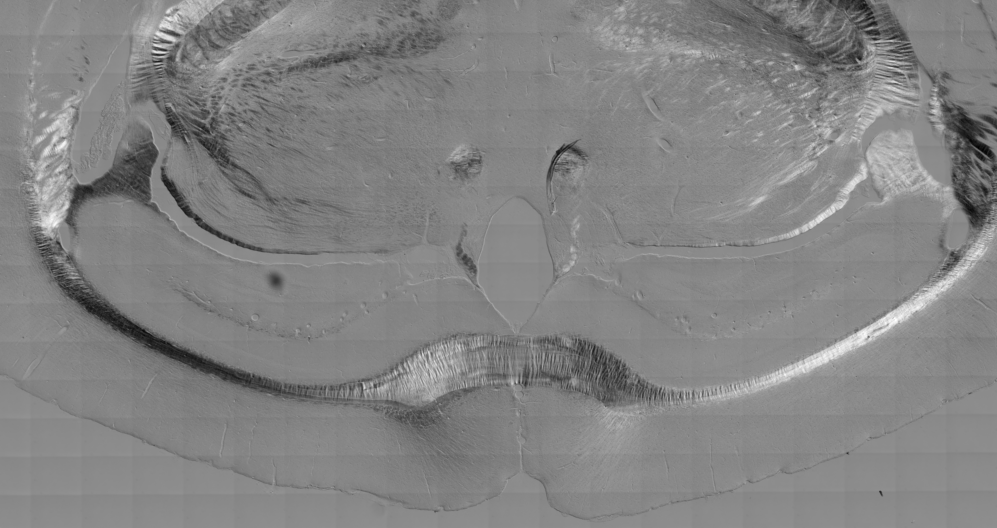

Note the bilateral symmetry in a slice of mouse brain imaged by Nomarksi optics.